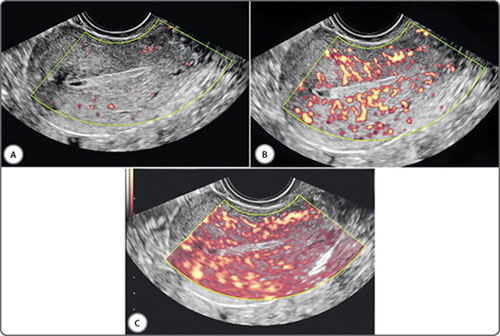

Adjusting the pulse repetition frequency (PRF) alters the sensitivity of Doppler for flow velocity (Figs 10A to C). A lower PRF will result in a lower scale, more sensitive for slower flows, but may cause aliasing artefacts.3 PRF should be ideally kept low when assessing vessels with low velocity blood flow (eg: ovarian stromal arteries) and be kept high when assessing vessels with high velocity blood flow (eg: uterine arteries).

Figs 10A to C: Doppler PRF settings: PRF settings should be kept low for vessels with low velocity blood flow and high for vessels with high velocity blood flow. This figure demonstrates the effect of PRF on velocity wave form on an ovarian stromal vessel. PRF is kept low (A), optimum (B) and high (C)

Similar to the basic B-mode or two-dimensional image, gain may be adjusted for Doppler. Increasing Doppler gain will amplify returning signals, resulting in more color or a stronger spectral signal (Figs 11A to C and Figs 12A to C). As in B-mode imaging, too much gain will result in noise and artifact.7 Doppler gain should be set so that the vessel lumen is filled with color but there is no spill outside.

Figs 11A to C: Doppler gain (Power Doppler): Increasing gain will amplify the returning signal resulting stronger Doppler signal. The gain is kept low (A), optimum (B) and high (C). Too much gain in (C) results in artefact signals